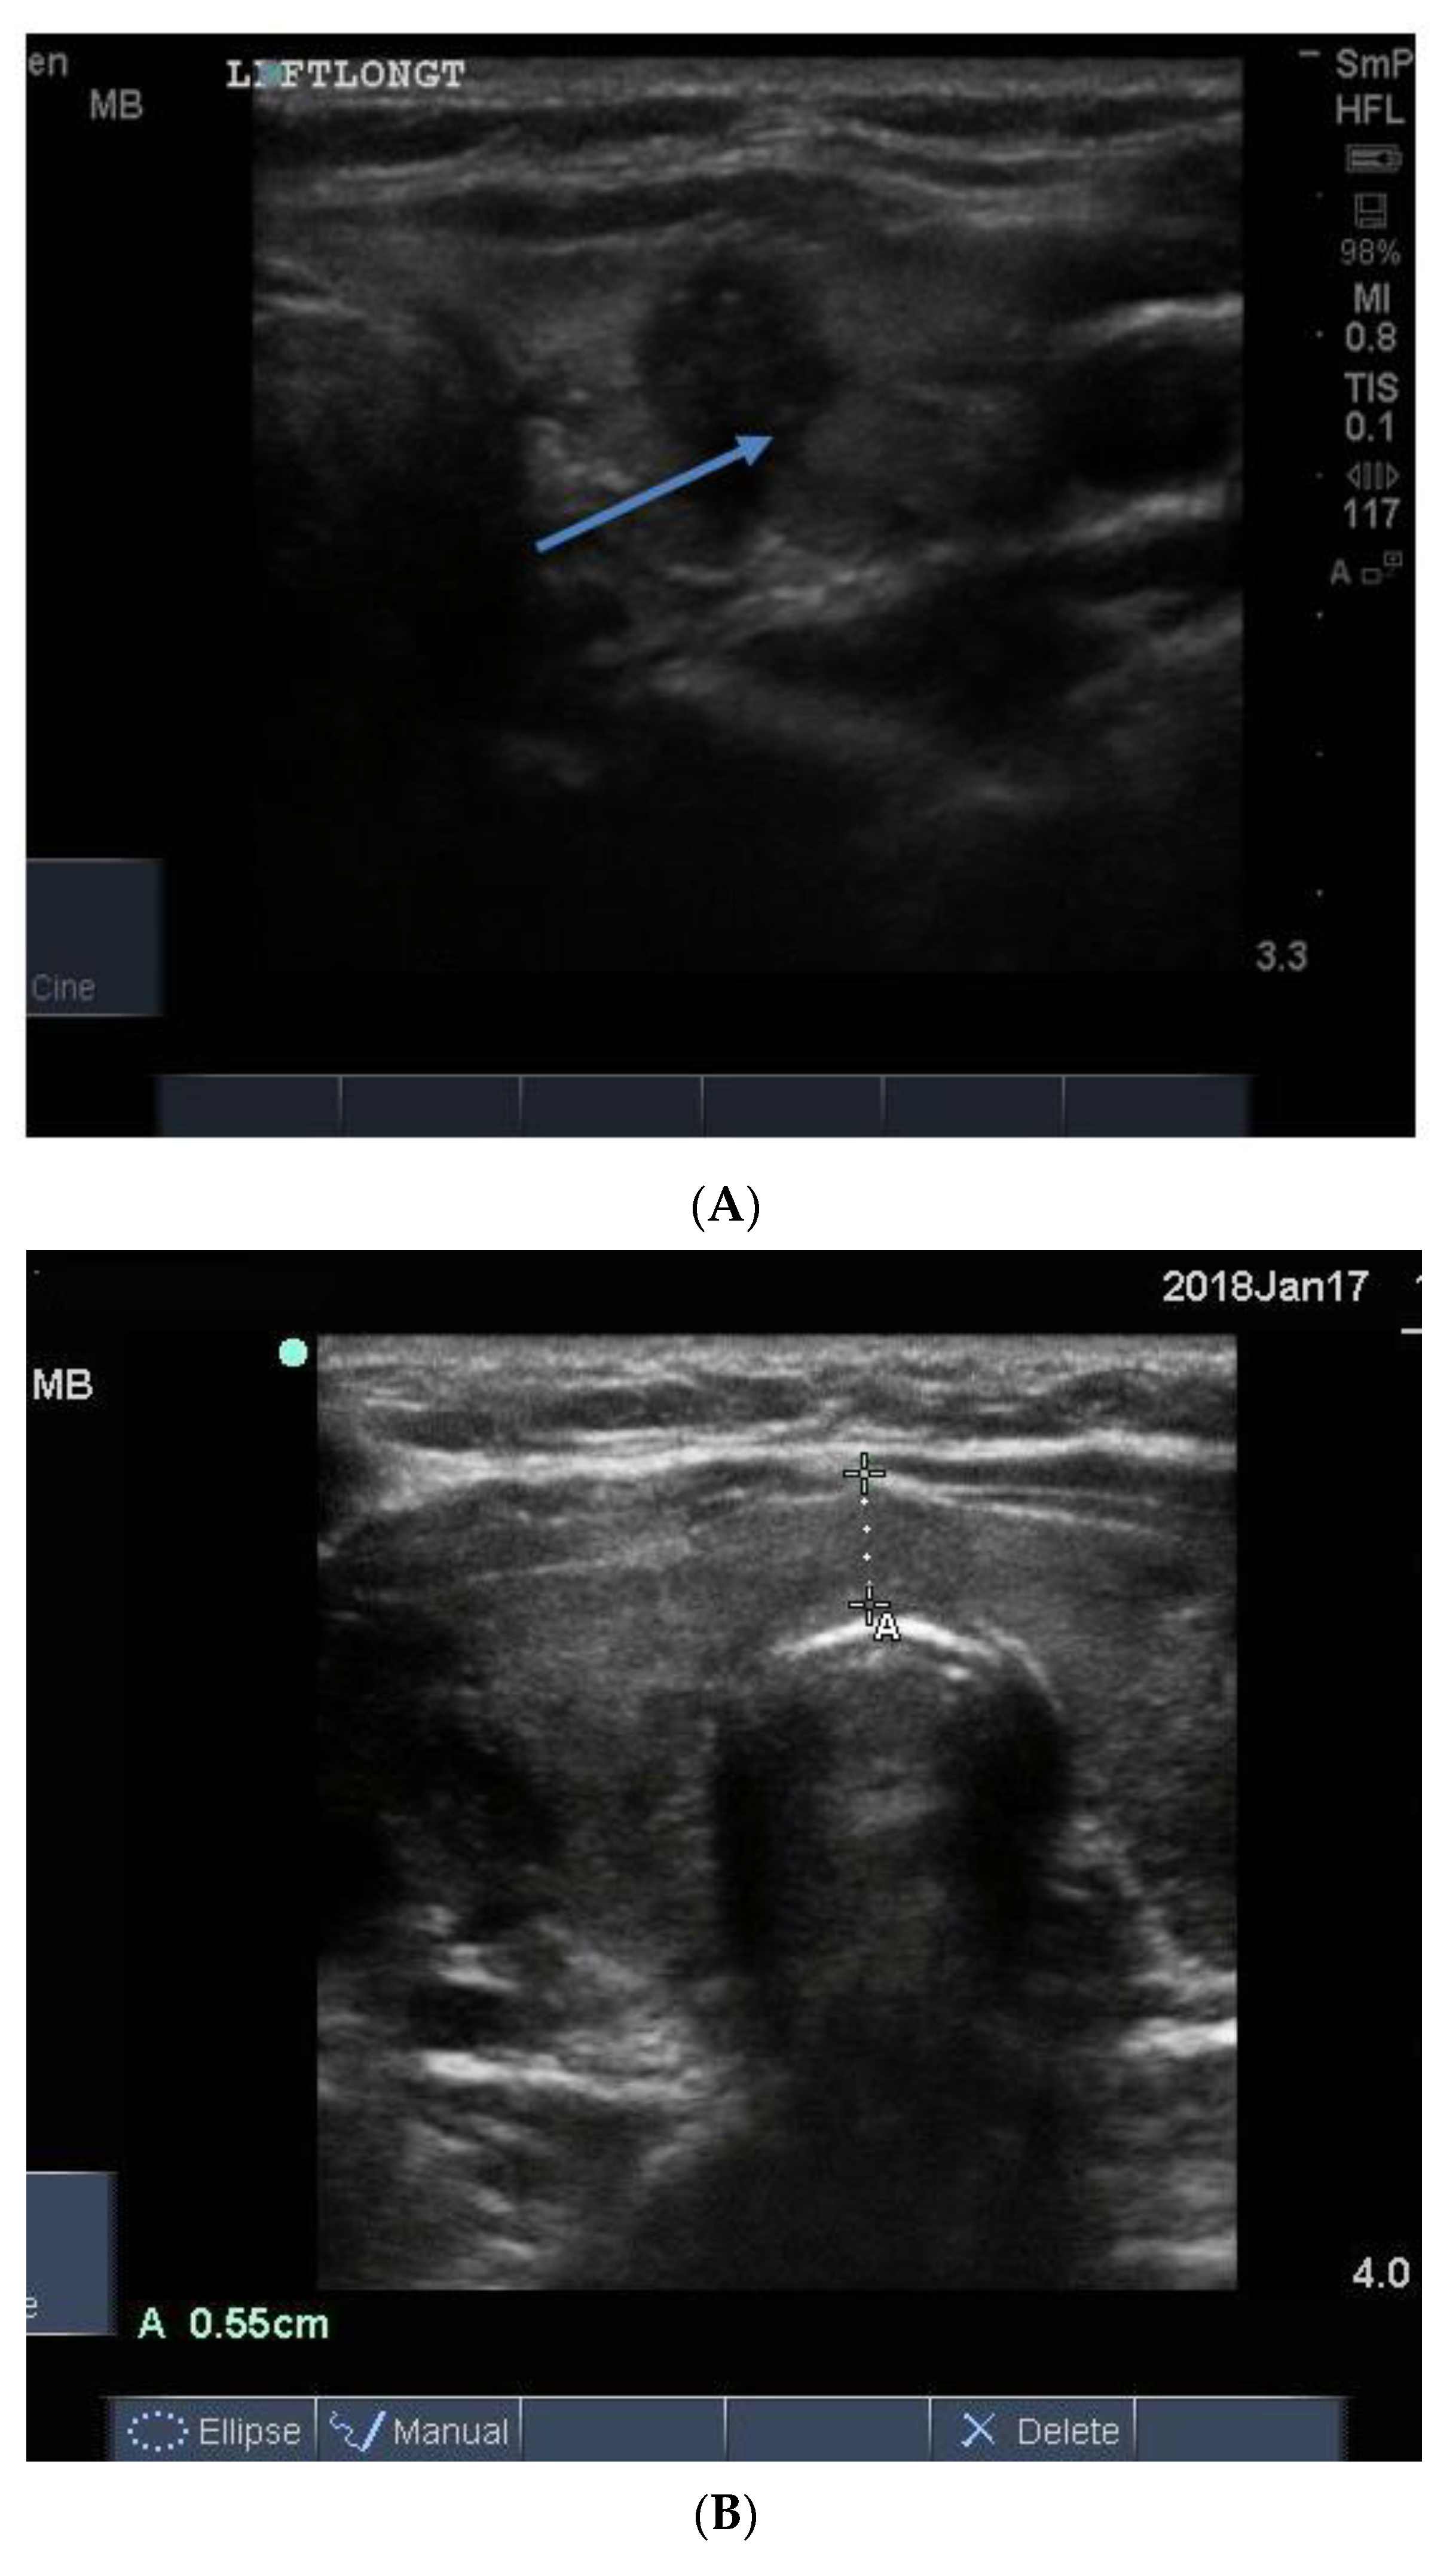

The blood supply in typical Graves’ disease is diffusely increased (and associated with a murmur), sometime up to 100 times normal, and the gland texture on ultrasound is usually heterogeneous (patchy) with a fine cystic appearance throughout, which reflects the diffuse nature of the inflammatory process (Figure 15). Following radio iodine treatment, the normal gland architecture is disrupted because the follicles are destroyed, and scar tissue predominates.

Figure 15.

Thyroid ultrasound from two patients with Graves’ hyperthyroidism. In (A) is shown an example of early Graves’ hyperthyroidism manifest as multiple small inflammatory and lymphoid lesions, often described by the consultant radiologist as “nodules” blue arrow. In (B) is shown an enlarged thyroid, with a thick isthmus and a generalized patchy hypo echoicity due to the lymphocytic inflammation and thyroid cell proliferation. In (C) is shown the increased vascularity in the thyroid of the patient shown in (B).